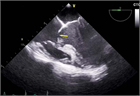

心室中隔欠損症(Ventricular Septal Defect, VSD)

1. 成人循環器内科医が診るVSDのほとんどは小欠損孔のrestrictive VSDとなる。なかにはsmall-moderate size(小~中欠損孔)restrictive VSDで小児期には血行動態的に影響がなかったが、成人期に心室コンプライアンス低下や体血管抵抗の上昇により左→右シャントが増加して左室拡大をきたすことがある。

1. 必要な検査と所見:身体所見、心エコー